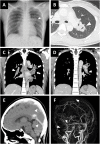

A 22-year-old woman was admitted to the hospital with complaints of headache and vomiting. Radiological examinations revealed cerebral sinus venous thromboses, pulmonary thromboembolism, and cavities in the left upper lung. Pulmonary tuberculosis was diagnosed based on sputum and gastric aspirate culture. Heparin followed by warfarin was administered. Anti-tuberculosis agents including rifampicin were also initiated. Since the effect of warfarin did not reach the therapeutic level because of interaction with rifampicin, edoxaban was administered and thromboses were ameliorated. This report illustrates rare thrombotic complications in a TB-induced hypercoagulable state and the potential benefits and safety of edoxaban in combination with rifampicin.